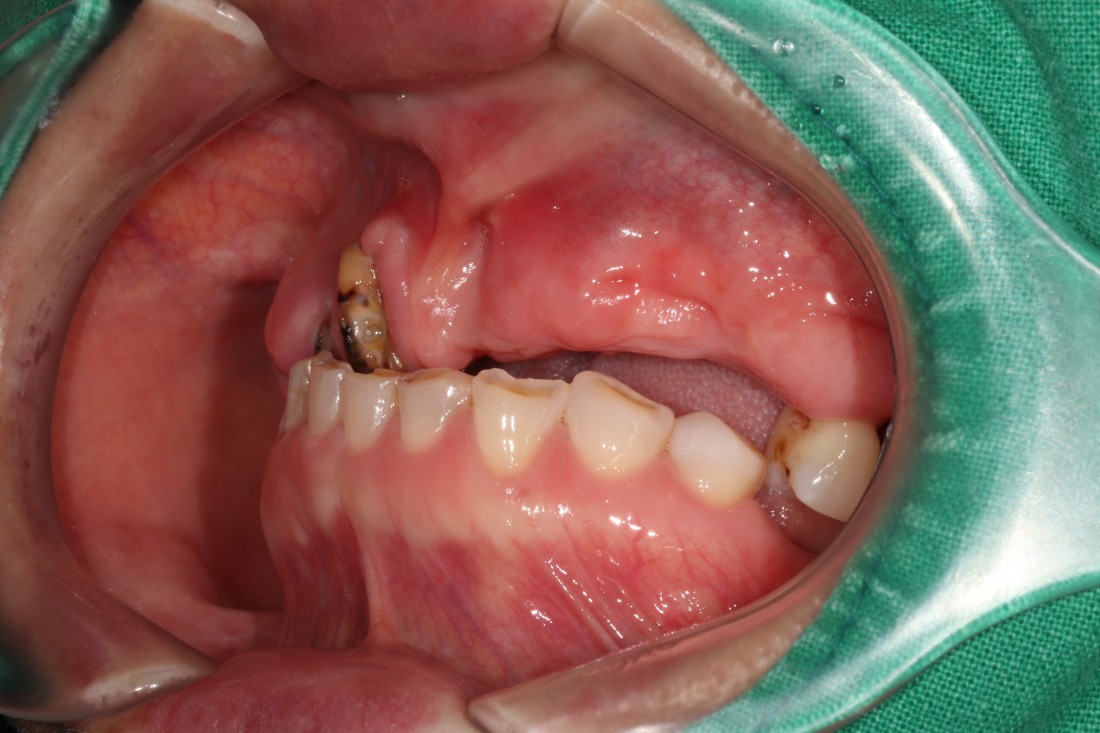

광주 상악임플란트를 해야하는 때가 오면

무엇보다도 '예쁘고 잘 씹어지게'

임플란트 진료를 받고싶으실텐데요.

광주 상악임플란트 치과는

4층 자체 치아기공소를 운영하고 있으며

보철물 디자인 퀄리티를

굉장히 중요하게 생각하고 진료하기 때문에

자연치아만큼 예쁘면서도

잘 씹어지는 광주 상악임플란트 진료를

보장할 수 있습니다.

만약 불편한 점이 생기셔도

자체 치아기공소에 바로 수정이 가능하여

빠르고 예쁘게, 잘 씹어지는

광주 상악임플란트를

완성하고 있습니다.